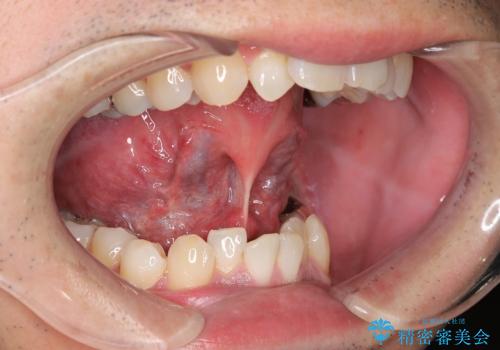

【舌小帯切除】ら行が言いづらい

- 滑舌が気になり来院されました。

舌小帯を形成することにより、滑舌の改善を図ります。

舌小帯形成では舌の可動域拡大や滑舌の改善を行うことが出来ます。

また、当日に処置が可能です。